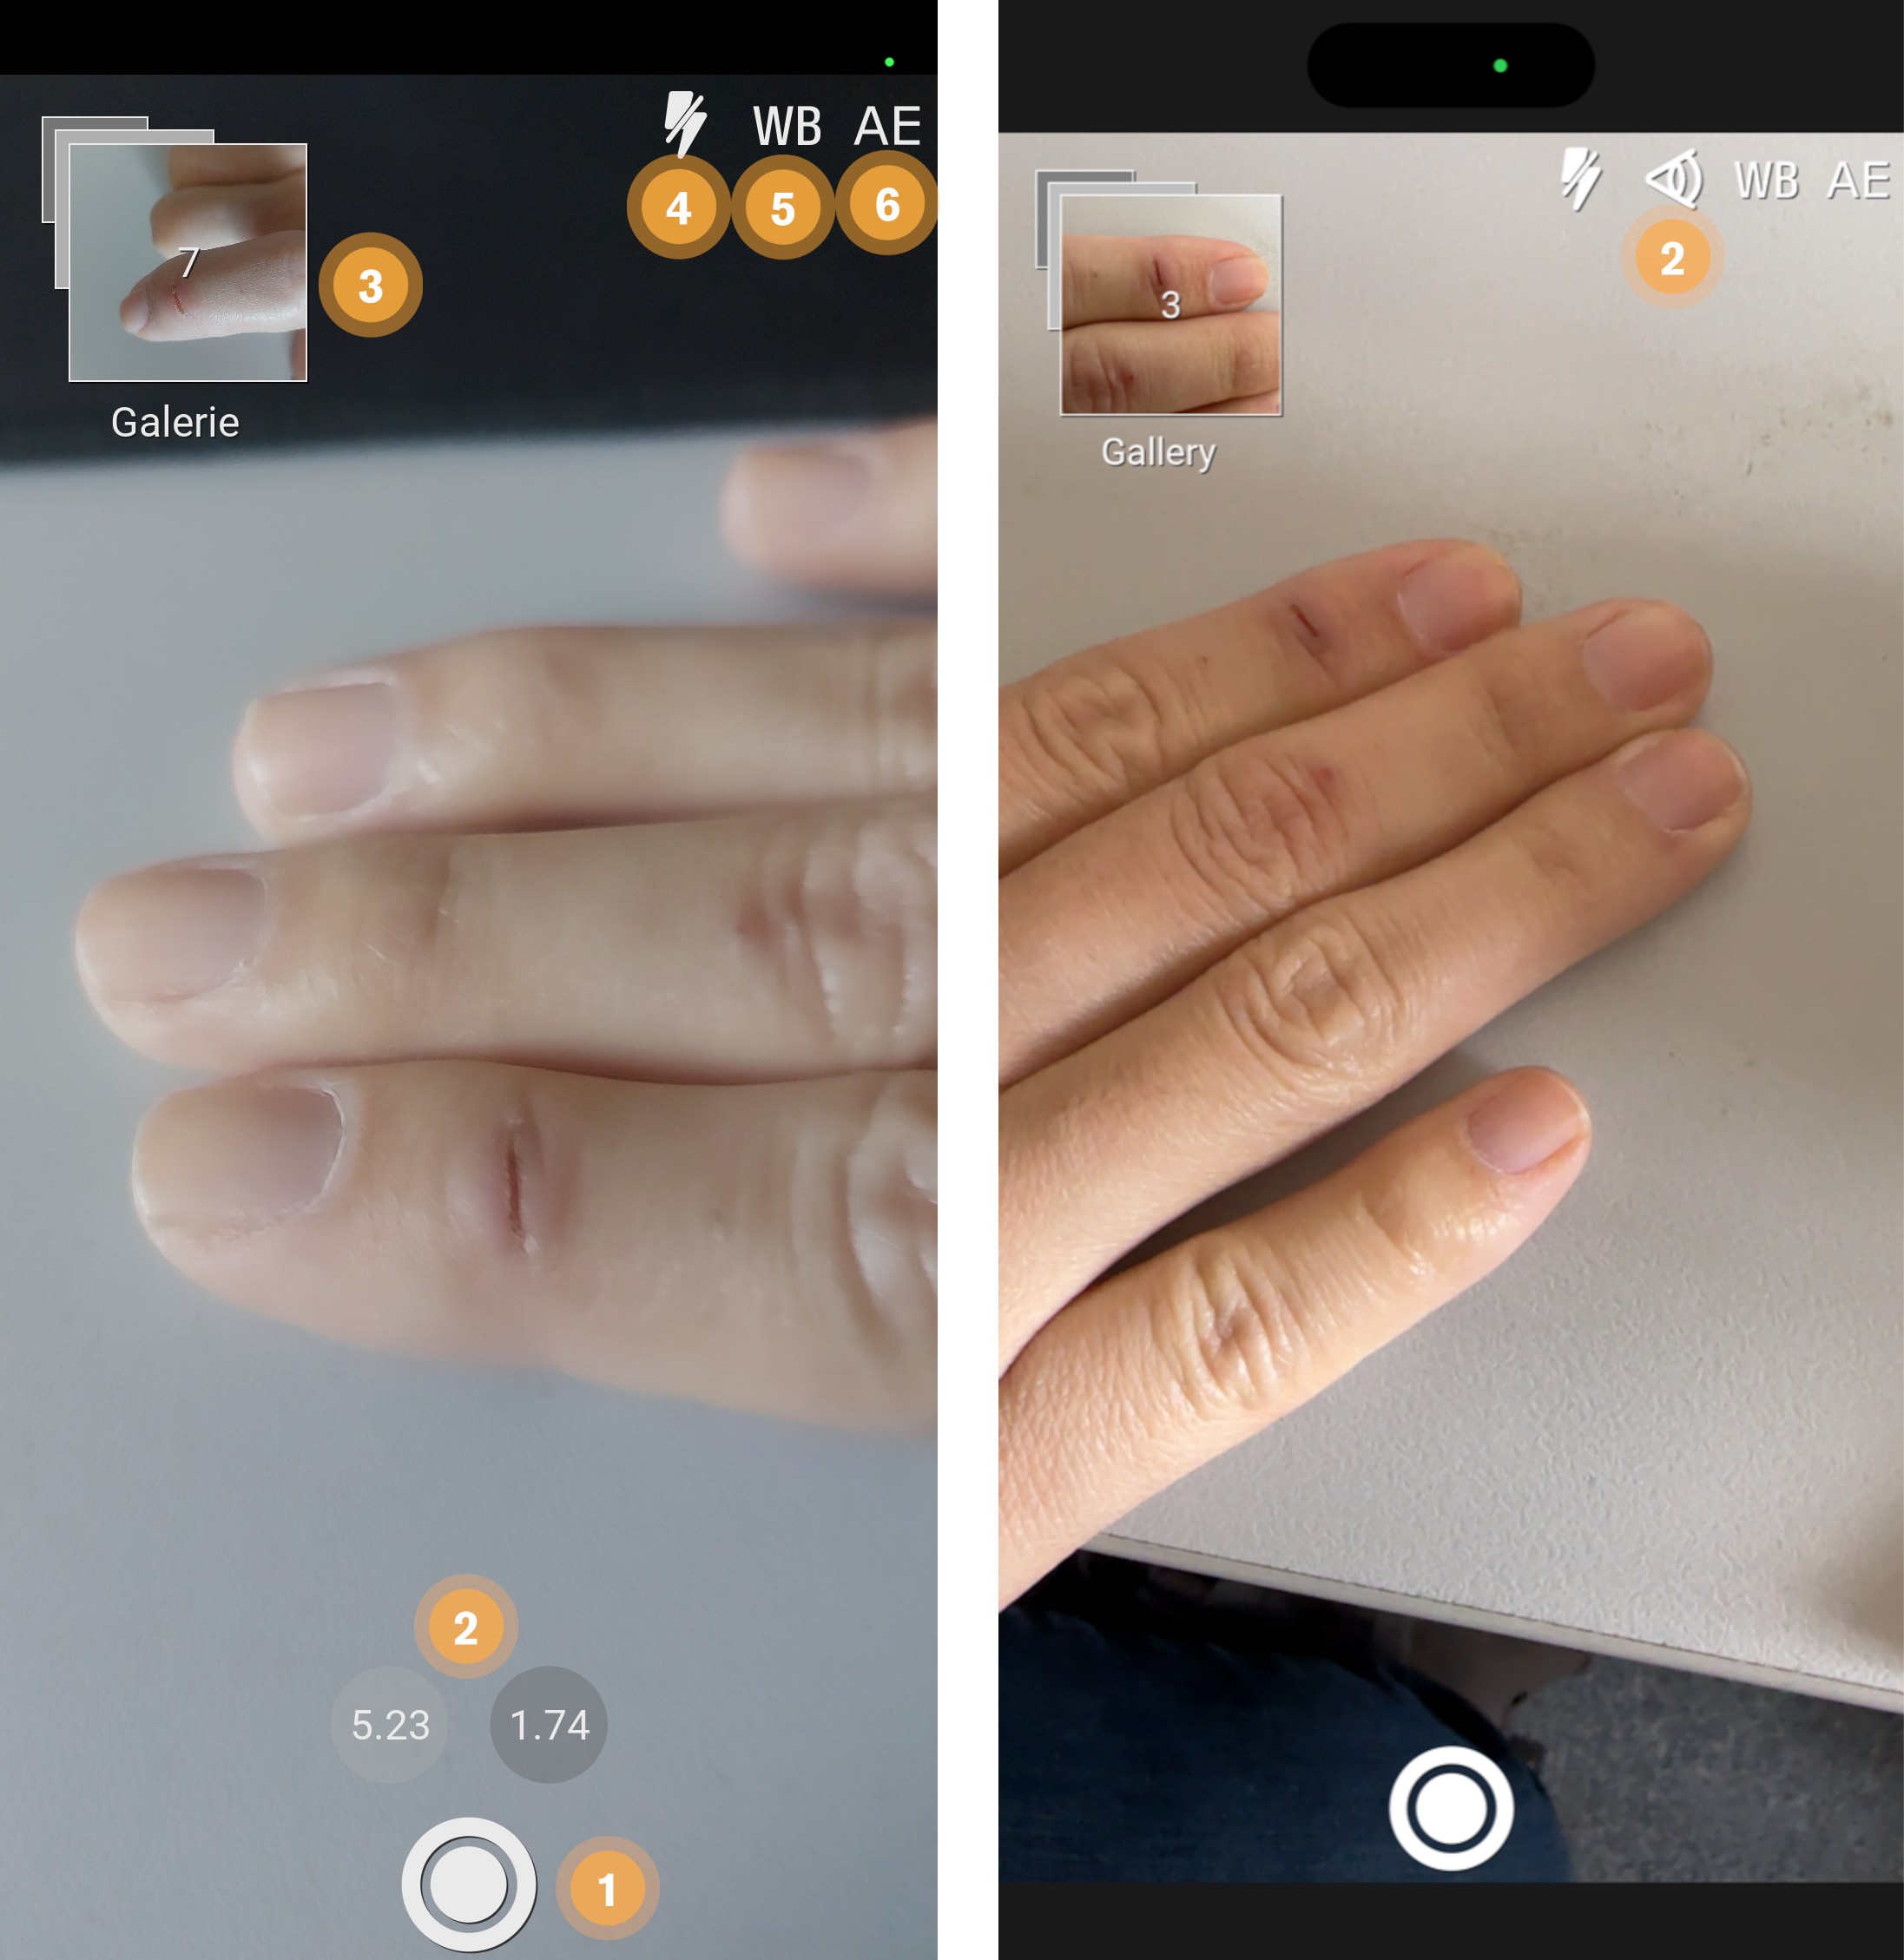

15.1. Camera

When you’ve captured all the photos you need press the photo stack (Point 3) to continue to the review process.

-

Shutter button to capture a image.

-

Select desired camera lens (only on devices with more than one camera).

-

Image stack of taken images. Click to return to gallery.

-

Enable, disable or set automatic flash operation.

-

Enable or disable automatic white balance adjustment.

-

Enable or disable automatic exposure adjustment.